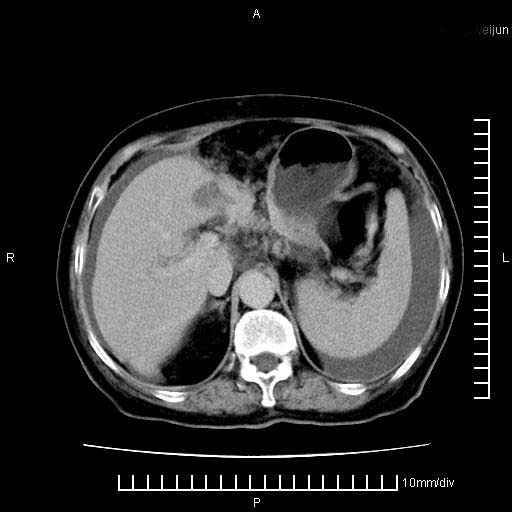

上腹疼痛月余,外院核磁诊断胰腺癌。现临床示右下腹可明显触及包块,可片子上怎么没有看到?

胰腺体部癌累及周围器官,腹膜、粘连

1。胰腺ca伴腹膜腔转移

胰腺体部癌累及周围器官,腹膜、粘连,临床摸到的可能是粘的组织

胰腺结构模糊,胰尾部见囊性包块,周围脂肪密度增高,左肾前筋膜增厚,胸水、腹水。不符合胰腺ca伴腹膜腔转移。考虑胰腺炎伴假性囊肿形成、胸腹腔积液。

1、考虑胰腺癌伴腹膜腔转移,胸腹水。

1)考虑胰腺癌并胰腺假性囊肿形成。2)肝内低密度灶,不排除转移。3)右肾盂积水。4)腹水。5)右侧胸腔积液并右肺下叶部分膨胀不全。

考虑胰腺ca伴腹膜腔转移、肝左叶转移、右肾积水。右胸腔积液。